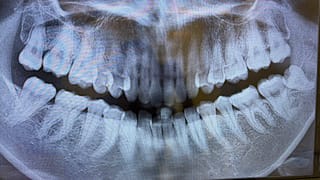

親知らず半埋伏抜歯の痛み・腫れは?|3本抜歯した私の経過と食事まとめ

親知らずの半埋伏抜歯はどれくらい痛い?腫れはいつまで?3本抜歯した私のリアルな経過と食事、抜歯当日の流れを体験ベースで詳しく紹介します。